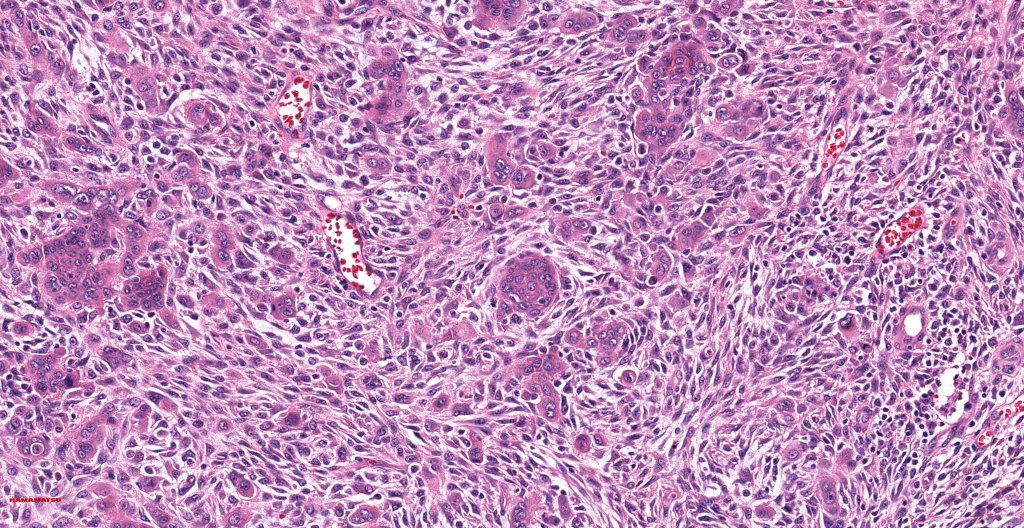

•Biphasic tumor

•Admixture of squamous carcinoma & pleomorphic spindled cell, osteoid, chondroid, MFH-like +/- osteoclast-like giant cells & rarely, smooth muscle, skeletal muscle, myofibroblastic or angiosarcomatous elements